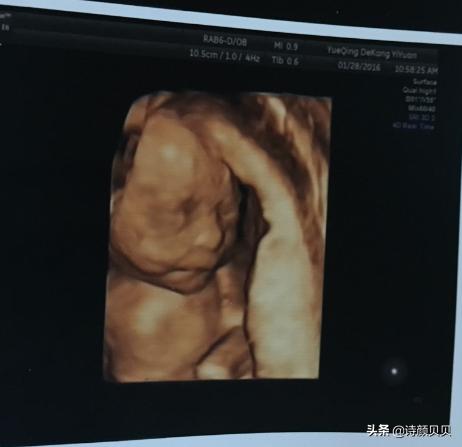

胚胎孕育过程中,受精卵常于30~40天形成胎囊,40~50天形成胎芽,50~60天形成胎心。但是在临床中常通过B超检查来观察胎心及胎芽,观察的时间为6~8周。

总的来说,40~50天形成胎芽,50~60天形成胎心,在6~8周左右可在B超下观察到。